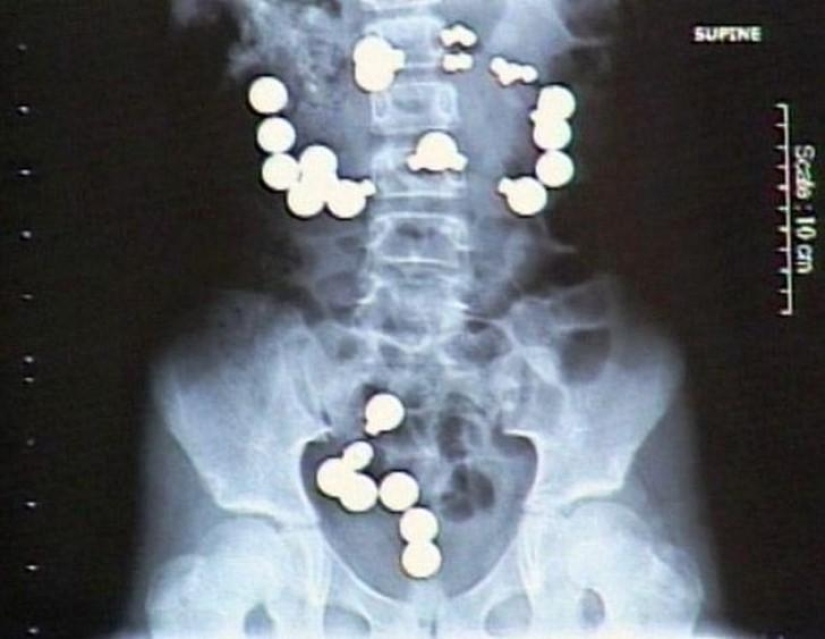

Imanes.

metanfetaminas